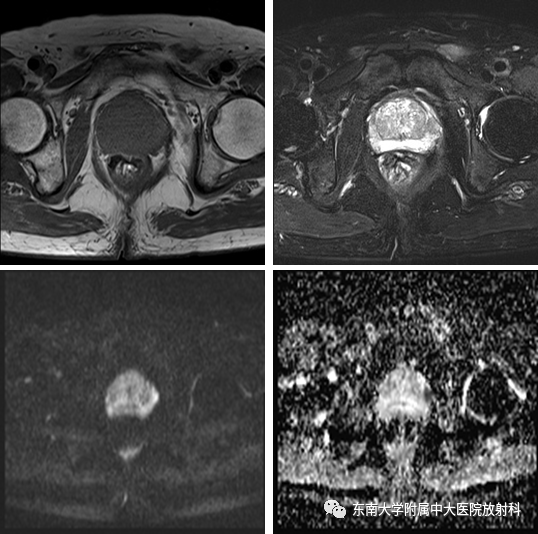

•患者1年前体检发现PSA升高,TPSA 19.793 ng/ml,无肉眼血尿,无尿频尿急尿痛,无畏寒发热。6天后复查TPSA 15.40 ng/ml,盆腔MR平扫示:左外周带3点钟方向异常信号结节,PI-RADS 4 级,遂行超声引导下前列腺穿刺活检,病理提示:正常前列腺组织。后患者于2019-10-24至我院复查TPSA 25.92 ng/ml

2018-10-23影像学表现